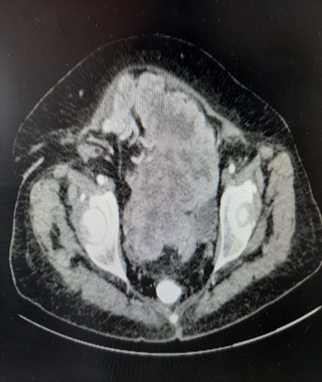

Figure 3 CT depiction of pelvic solitary fibrous tumor.

Figure 4 CT depiction of pelvic solitary fibrous tumor.

Figure 5 CT depiction of pelvic solitary fibrous tumor.

Abdominal CT revealed presence of enormous solid lesion with small lobular posterior line, which also bears cystic elements, necrosis and calcifications in its interior.

Formation diameter among 15,3X14,1X14,8 cm, obfuscating extended segments of descent colon and recto sigmoid which are in incomplete development, coming in contact with the uterus and bilateral adnexa, obfuscating them as well.

It also exerts pressure on the urinary tract. Other formations free of malignancy. Thorax CT did not reveal any pathological formations. Resuming all appropriate imaging findings, optimal therapeutic strategy reflected surgical dissection of the lesion and optimal staging. Due to size tumor, suprahypocephalic section entering the peritoneal cavity was performed.